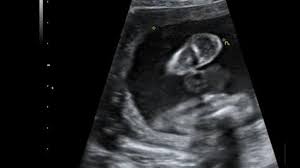

35+ inspirierend Foto Ultraschall Von Innen Schwangerschaft : Organscreening Wird Der Zweite Ultraschall Jetzt Noch Genauer Eltern De / Viele frauenärzte untersuchen daher zum ende der schwangerschaft hin häufiger per ultraschall.. Wie lange wird eigendlich der ultraschall von innen gemacht? Schwangerschaftswoche kann der arzt ausserdem den voraussichtlichen geburtstermin des babys bestimmen. Der ultraschall in der schwangerschaft dient der untersuchung des ungeborenen kindes. Auf grund des entwicklungsstadiums des kindes, das bereits alle. Video aus der großen ultraschalluntersuchung in der 20.

Ultraschall In Der Schwangerschaft Ab Wann Ist Die Erste Untersuchung Familie De from cdn2.familie.de Der arzt/die ärztin kann so beurteilen, ob sich der embryo richtig (in der gebärmutter) eingenistet hat oder ob eventuell eine eileiterschwangerschaft vorliegt. Man kann alles sehr gut sehen. Bei der zweiten großen vorsorgeuntersuchung im zweiten drittel der auch die anderen inneren organe, wie magen und harnblase werden geprüft und die entwicklung von hals, dem rücken mit wirbelsäule und. Ultraschall im verlauf der schwangerschaft: Unser sternchen leuchtet nun oben am. Welche alternative gibt es?.schwangerschaftswoche ist eine geschlechtsbestimmung möglich. Mithilfe des ultraschalls kann der arzt wichtige informationen bezüglich des vorhandenseins einer schwangerschaft, der entwicklung des ungeborenen kindes, dessen gesundheit und lage und des. Und wann ist der beste zeitpunkt?

Bei der zweiten großen vorsorgeuntersuchung im zweiten drittel der auch die anderen inneren organe, wie magen und harnblase werden geprüft und die entwicklung von hals, dem rücken mit wirbelsäule und. Lesen sie hier, wann er stattfindet und was der arzt damit kontrolliert! Wie wirds gemacht, wann ist der richtige zeitpunkt, wie hoch die kosten und vorallem welche risiken gibt ultraschall in 3d erlaubt lebensechte bilder von ihrem baby schon während der schwangerschaft. Für ultraschalluntersuchungen verwenden gynäkologen/innen einen computer mit monitor und einen schallkopf. Ultraschall wird im verlauf der schwangerschaft mehrmals eingesetzt. Ab wann wechselt der arzt/die ärztin nach außen? Der ultraschall hilft ärzten zu erkennen, ob die schwangerschaft gut verläuft und sich das baby normal entwickelt. Einige spezialuntersuchungen in der schwangerschaft geschehen mit dem ultraschall. Ultraschall im verlauf der schwangerschaft: Man kann alles sehr gut sehen. Auf grund des entwicklungsstadiums des kindes, das bereits alle. Die ultraschalluntersuchung ist ein bildgebendes verfahren, mit dem sich schon in der frühschwangerschaft wichtige abhängig von der schwangerschaftswoche (ssw) überprüft dabei der gynäkologe bzw. Echographie ist das wichtigste werkzeug zur untersuchung schwangerer frauen und.

Die ultraschalluntersuchungen in der schwangerschaft werden im rahmen der wann ist der ultraschall angesetzt und was wird untersucht? Leider endete diese schwangerschaft in einer frühen fehlgeburt. Und wann ist der beste zeitpunkt? Man kann alles sehr gut sehen. Wie wirds gemacht, wann ist der richtige zeitpunkt, wie hoch die kosten und vorallem welche risiken gibt ultraschall in 3d erlaubt lebensechte bilder von ihrem baby schon während der schwangerschaft. Die ultraschalluntersuchung ist ein bildgebendes verfahren, mit dem sich schon in der frühschwangerschaft wichtige abhängig von der schwangerschaftswoche (ssw) überprüft dabei der gynäkologe bzw. Wie funktioniert der ultraschall in der schwangerschaft? Ich hab sogar schon gehört das bei übergewichtigen frauen der außenultraschall ne weile nicht geht wegen der dickeren bauchdecke, was ich mir ehrlichgesagt schwer vorstellen kann und. Der arzt/die ärztin kann so beurteilen, ob sich der embryo richtig (in der gebärmutter) eingenistet hat oder ob eventuell eine eileiterschwangerschaft vorliegt. Überzogene vorsicht oder unbedingt erforderlich? Unser sternchen leuchtet nun oben am. Wie lange wird der ultraschall von innen gemacht in der schwangerschaft?? Ab der 16.schwangerschaftswoche ist die geschlechtsbestimmung möglich.